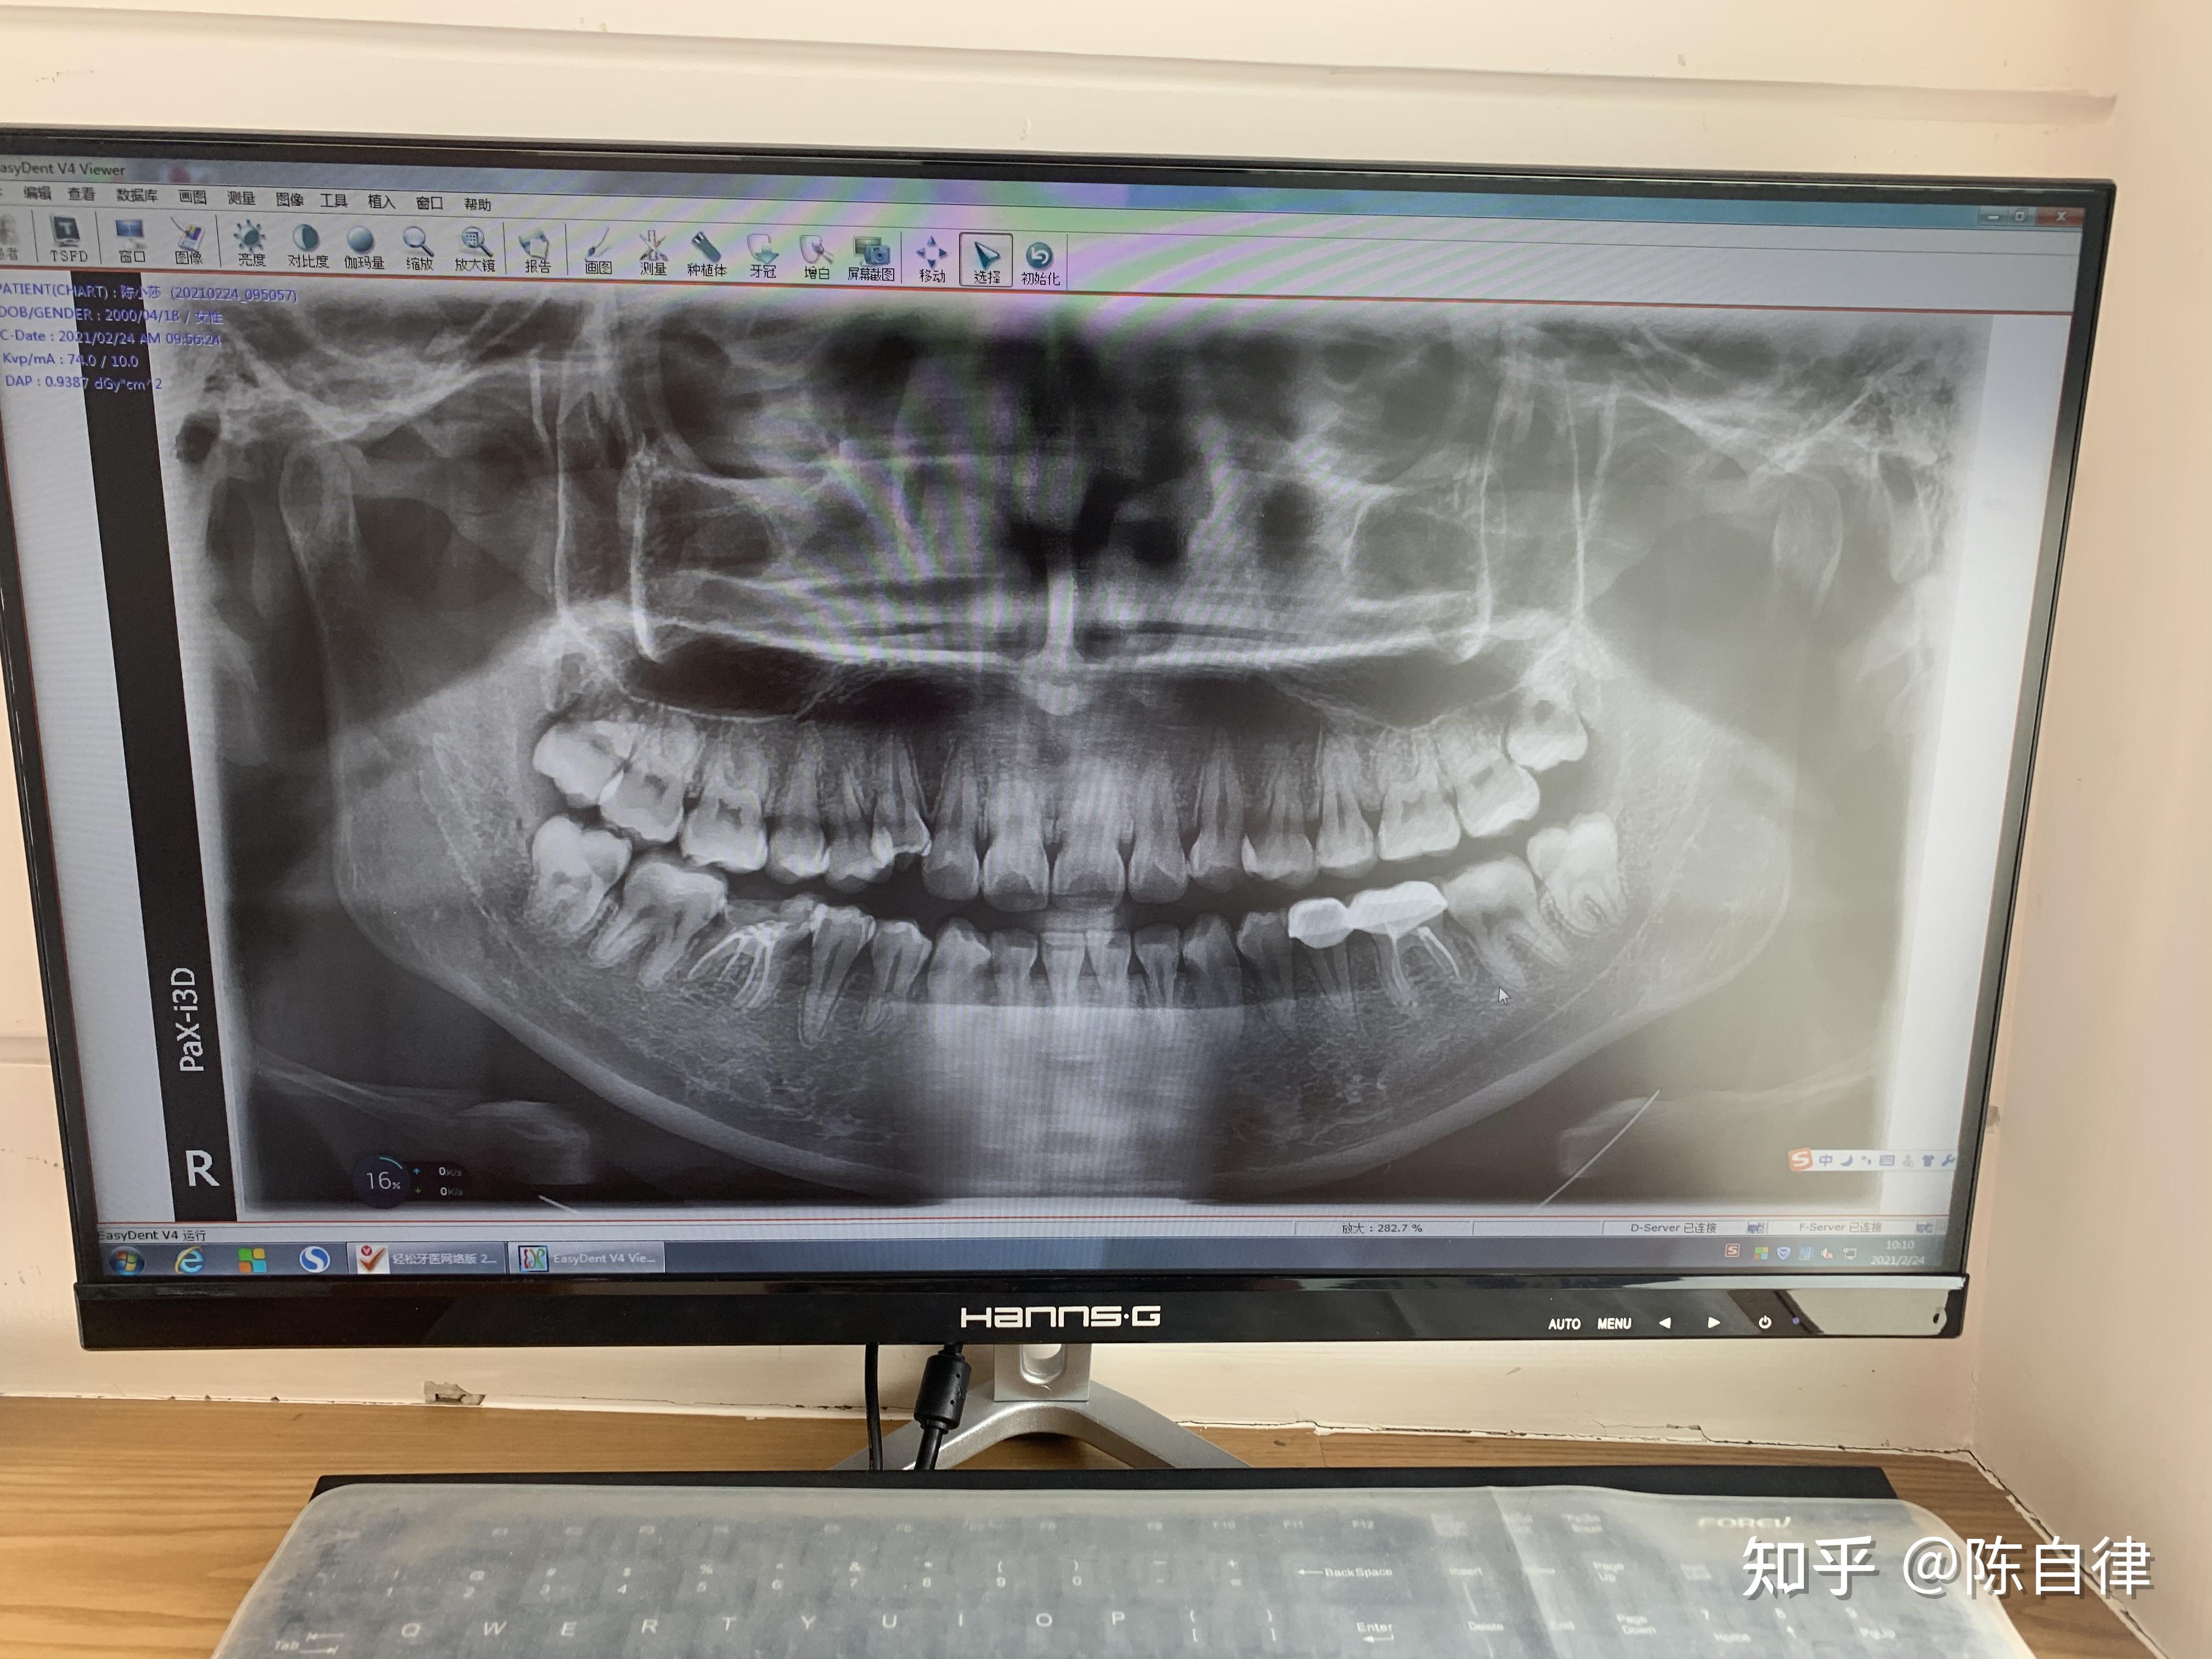

牙片子图片

2,阻生牙拔除通过牙片,医生可以了解牙体龋坏的程度和根尖区情况,为患